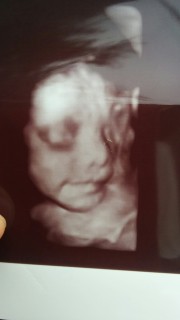

初めてお顔が鮮明に写りました!1246gで逆子もなおり安心(;_;) パパもママも既にメロメロです(*^◯^*)元気に産まれておいでね。